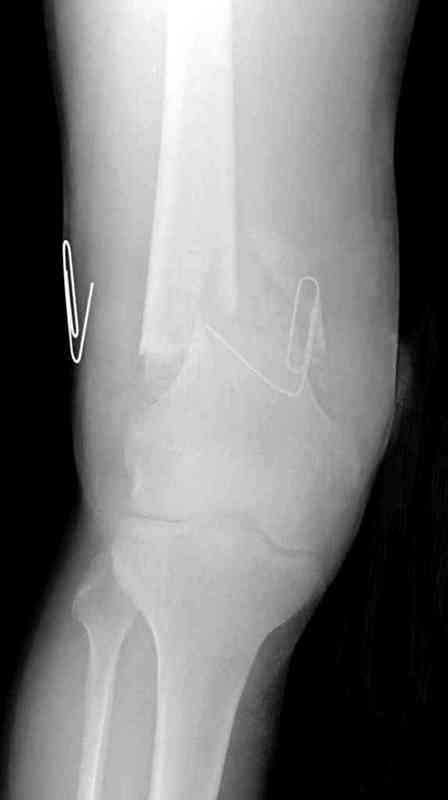

На третий день после Irrigation & Debridment закрыли все раны за исключением компартментальной раны из-за отека, медиально в дефект кости установили Putty Grafton Bone Substitute. На компартментальную рану вакуум и мероприятия по сближению краев раны резиновой стяжкой.

На 9й день с момента травмы ушили рану без натяжения. Больной получает реабилитацию, движения коленного сустава с помощи CPM-continuous passive motion machine. Сегодня выписан.

|

Нет, те же сосудистые держалки, их можно применить для сближения краев ран, только надо иметь stapler для ушивания. Резина прикрепляется с помощью скоб по краям раны (как на рисунке) и затягивается. Сверху вакуум VAC, через пару дней почти приближенные края

закрывается без натяжения.